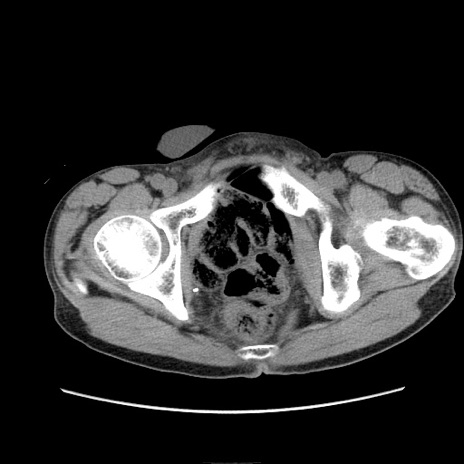

症例11(横断像)

【症例】 60歳代男性

【主訴】 下腹部痛

【現病歴】 本日夜中より下腹部痛の症状認め、受診。

【既往歴】 膀胱癌(膀胱全摘+尿管皮膚瘻術) 、胃癌術後

【身体所見】 BT 35.3℃、PR 58/min、BP 136/98mHg、腹部平坦、軟、腸蠕動音±、ストマ留置あり、左上腹部~正中部に圧痛あり、反跳痛なし。

【データ】WBC 5100、CRP0.01